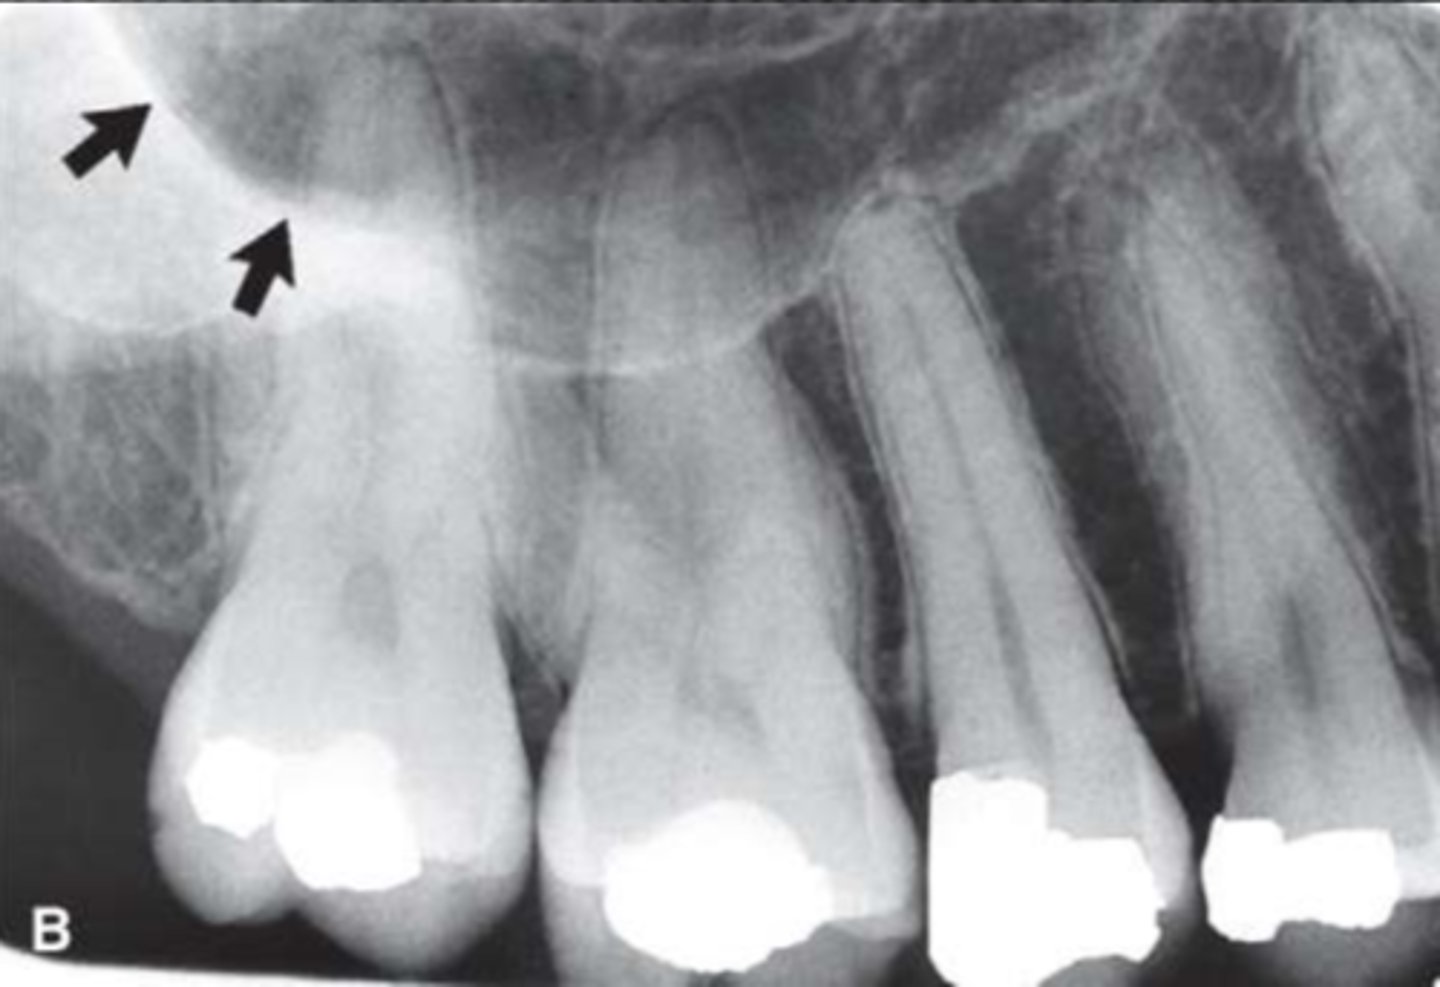

37

Nasopalatine (incisive) foramen

Identify the round, ovoid radiolucent structure indicated by the black arrows.

<p>Identify the round, ovoid radiolucent structure indicated by the black arrows.</p>

38

New cards

Nasopalatine canal

Identify the straight, radiopaque lines indicated by the white arrows.

<p>Identify the straight, radiopaque lines indicated by the white arrows.</p>